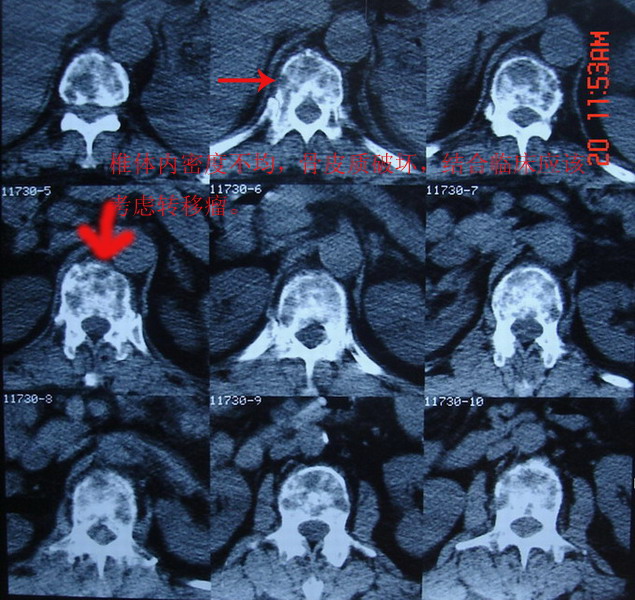

标题: CT7805:怀疑腰椎转移瘤 [打印本页]

男,65岁,临床诊断左肺ca,现腰痛半月余

自胸11至腰5椎体ct表现与上图相似

椎体内密度不均匀,见斑片状密度增高影,其内有更低密度区 部分皮质破坏 考虑 椎体转移瘤可能性大

椎体内密度不均匀,见斑片状密度增高影,其内有更低密度区 部分皮质破坏

考虑 椎体转移瘤可能性大